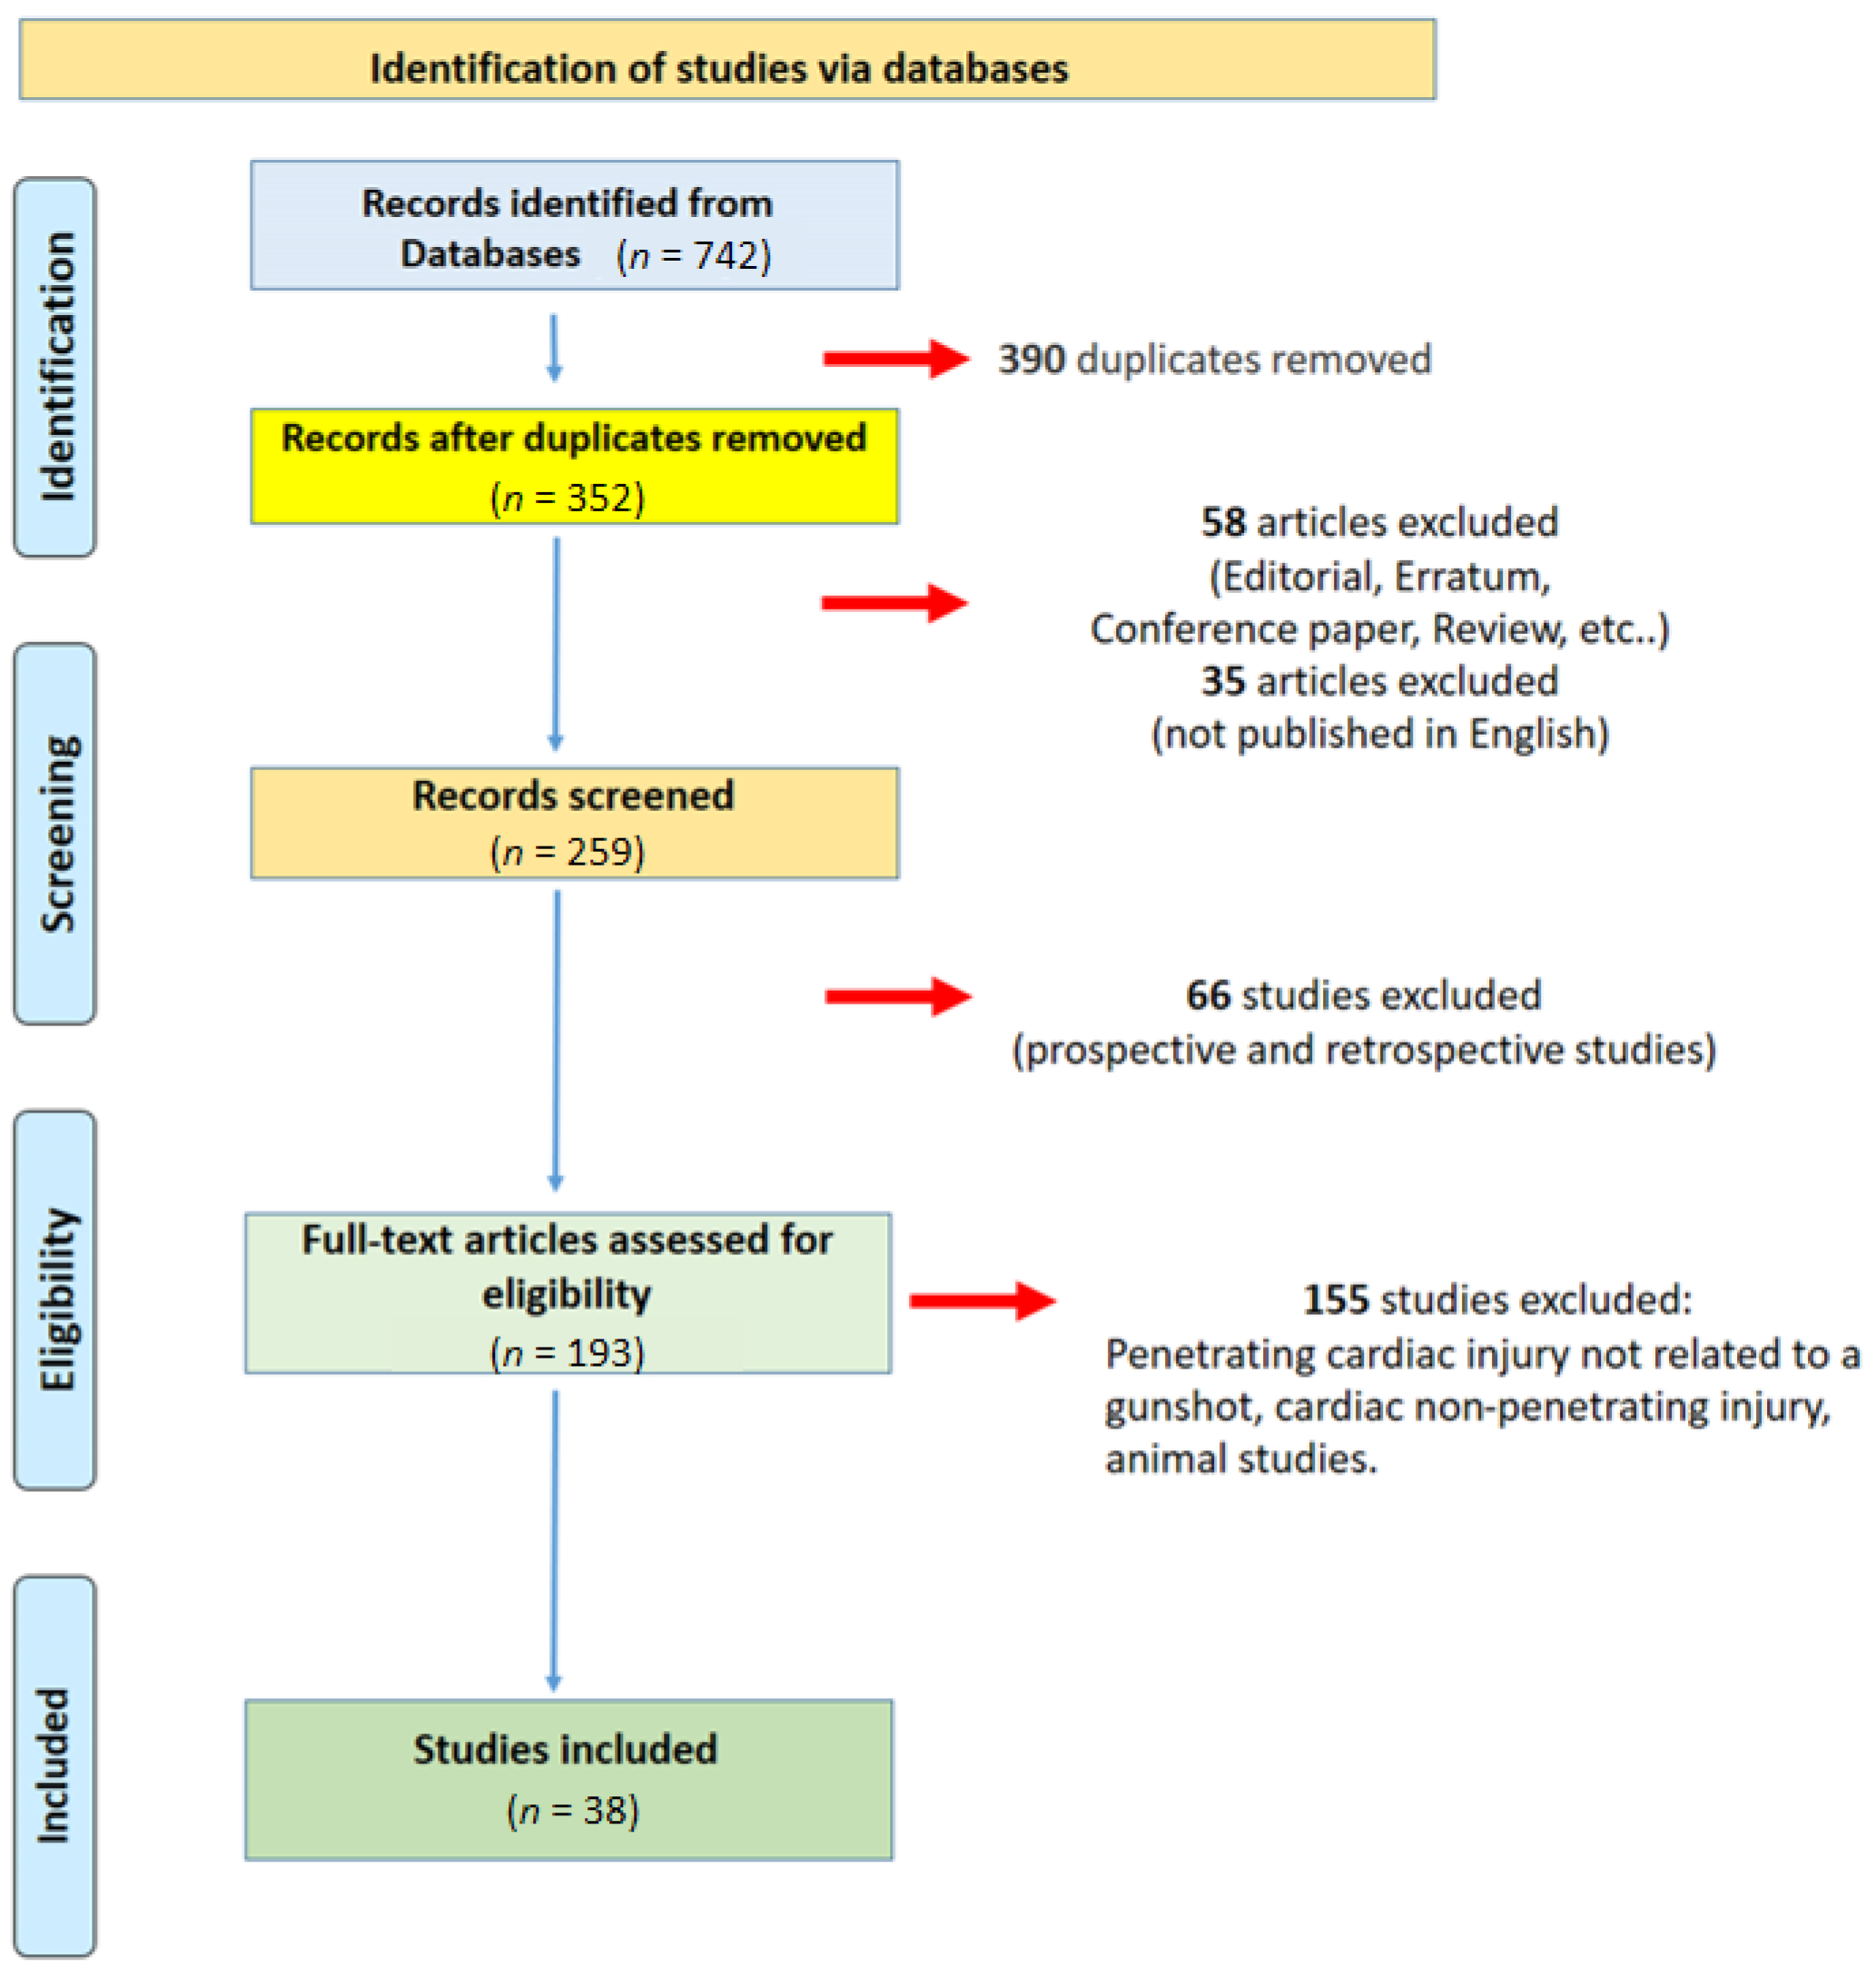

Healthcare | Free Full-Text | Systematic Review of Penetrating Cardiac …